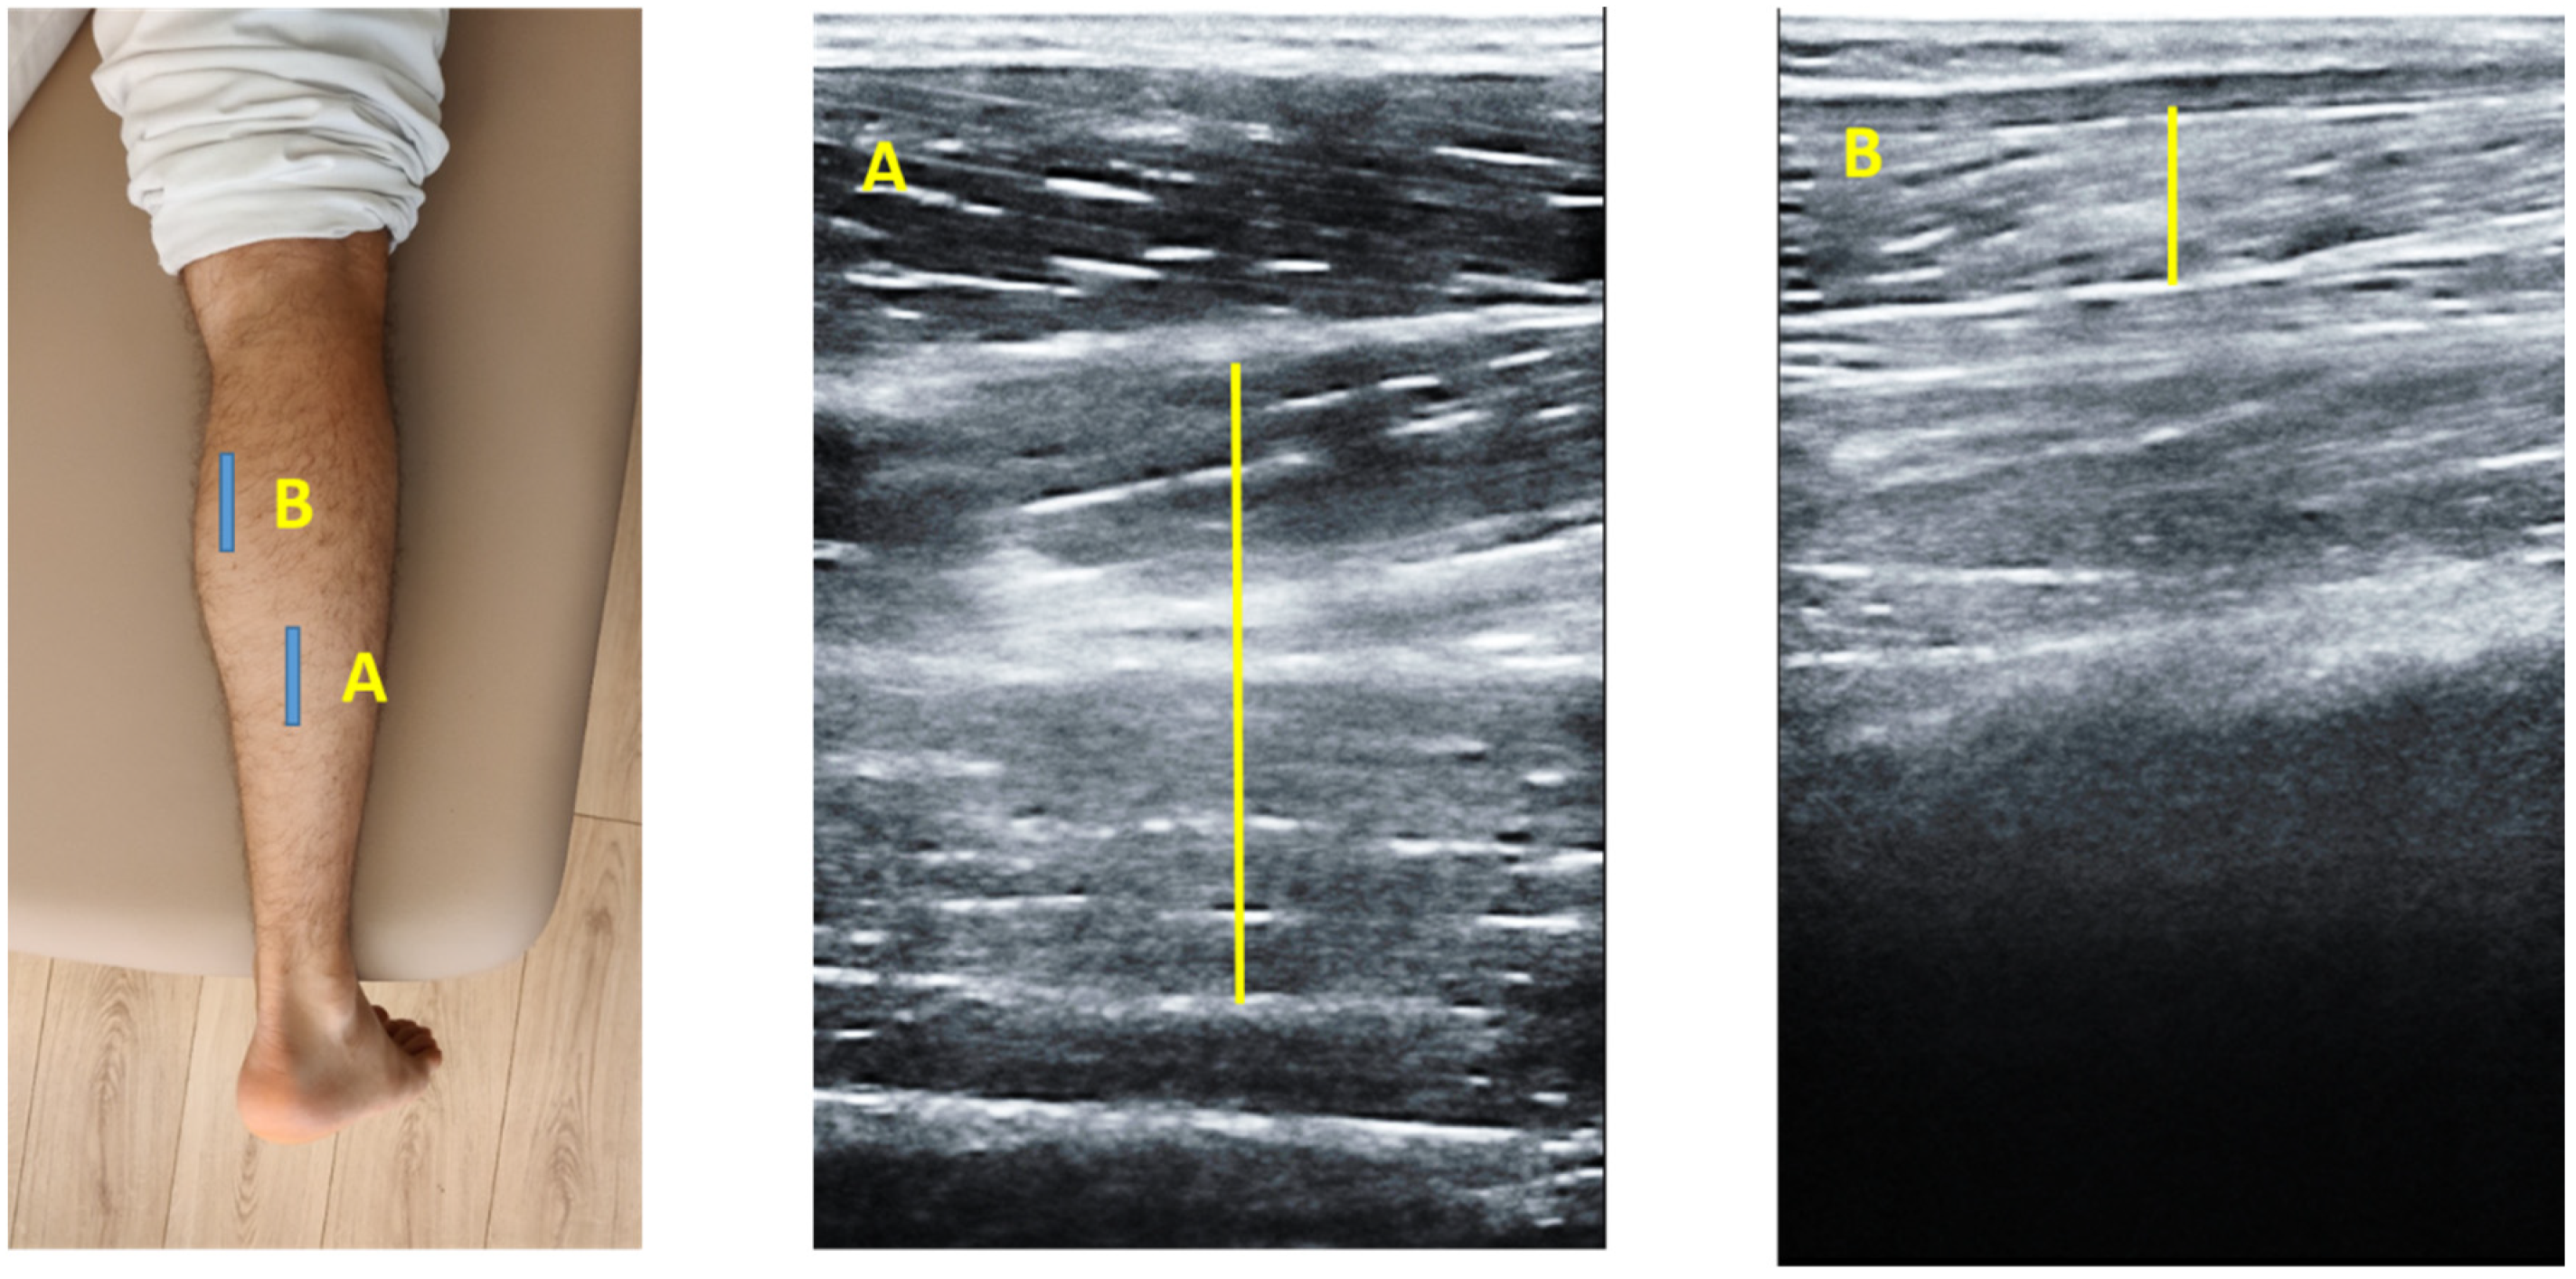

2.3. Ultrasonography Examination

2.4. Image Analysis